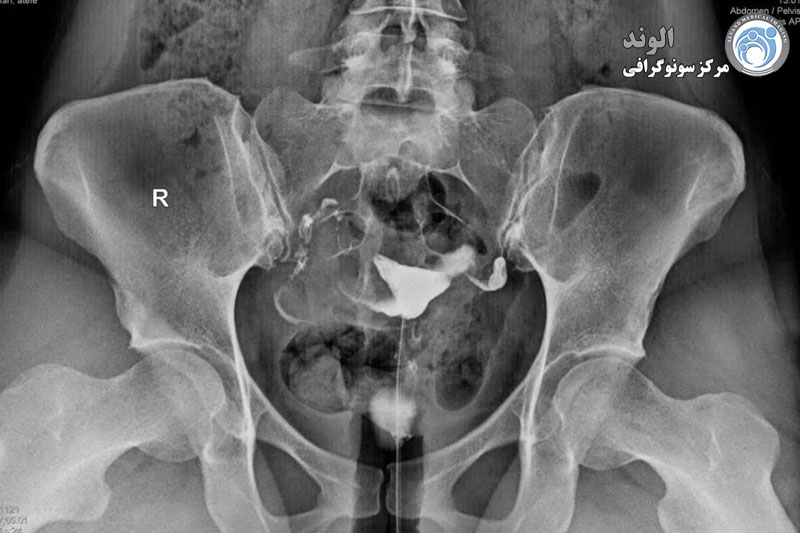

بیمار در وضعیت زنان (به پشت خوابیده، زانوهای خم شده و از هم باز)، زیر دستگاه اشعه ایکس قرار می گیرد. پزشک یک اسپکولوم را وارد واژن میکند، سپس یک کانولا را در دهانه رحم قرار میدهد که از طریق آن یک ماده حاجب تزریق میکند. این به داخل رحم و لوله های فالوپ گسترش می یابد. اشعه ایکس برای مشاهده پیشرفت خوب محصول و تجسم اندام ها گرفته می شود.

هیستروسالپنگوگرافی توسط رادیولوژیست انجام می شود. معاینه بدون بیهوشی انجام می شود. بیمار در موقعیت "زنان و زایمان" مستقر می شود. پزشک اسپکولوم را قرار می دهد، دهانه رحم را ضد عفونی می کند و سپس یک پروب را با روش طبیعی وارد رحم می کند. او به تدریج ماده حاجب را تزریق می کند. به طور معمول، ماده حاجب به تدریج رحم و لوله های فالوپ را کدر می کند تا زمانی که به حفره صفاقی منتقل شود.

در اصل، HSG یک ارزیابی رادیوگرافی از حفره رحم و لوله های فالوپ با استفاده از فلوروسکوپی سرپایی بلادرنگ با تزریق ماده حاجب رادیویی مات از طریق کانال دهانه رحم را نشان می دهد. کانال دهانه رحم، کانتور حفره رحم و لومینای رحم و لوله شامل بخش های قرنیه، ایستمی و آمپولری و تعیین

بیمار باید در وضعیت لیتوتومی پشتی روی میز فلوروسکوپی قرار گیرد و بازوهایش به سمت جانبی یا پشت سر جابجا شده باشند و هیچ تکه فلزی لباس با میدان معاینه تداخل نداشته باشد. سپس یک اسپکولوم در واژن قرار داده می شود و دهانه رحم به روش معمول مشاهده و تمیز می شود.

تشخیص انسداد لوله فالوپ

هیستروسالپنگوگرافی (HSG) نوعی اشعه ایکس است که برای بررسی داخل لوله های فالوپ برای کمک به تشخیص انسداد و محل وجود این بلوک استفاده می شود. در طول هیسترو سالپنگوگرافی ، پزشک از طریق دهانه رحم یک رنگ را به رحم و لوله های فالوپ وارد می کند.

این رنگ به پزشک کمک می کند تا قسمت بیشتری از داخل لوله های فالوپ شما را در عکس اشعه ایکس ببیند. هیسترو سالپنگوگرافی معمولاً در بیمارستان ها و مراکز رادیووژی انجام می شود. این باید در نیمه اول چرخه قاعدگی بین 14 تا 18 روز پس از پریود انجام شود. در این روش عوارض جانبی نادر است، اما ممکن است نتایج مثبت کاذب داشته باشد.

روش HSG و SSG

HSG یک روش اشعه ایکس برای تعیین اینکه آیا لوله های فالوپ باز هستند و شکل حفره رحم طبیعی است یا خیر. SSG شبیه HSG است اما سونوگرافی است.

HSG و SSG در روز 5 تا 12 سیکل قاعدگی زمانی که قاعدگی متوقف شده و تخمک گذاری هنوز اتفاق نیفتاده است، انجام می شود، بنابراین حاملگی زودرس مختل نمی شود. در این روشها، یک اسپکولوم واژینال قرار داده میشود (همان اسمیر غربالگری دهانه رحم) و یک لوله ظریف از طریق دهانه رحم و داخل رحم وارد میشود تا رنگ به داخل رحم و لولهها منتقل شود.

هیستروسالپنگوگرام (HSG) روشی است که از اشعه ایکس برای بررسی لوله های فالوپ و رحم استفاده می کند. نیاز به عکس برداری به این معنی است که این آزمایش در بخش اشعه ایکس انجام می شود.

مرحله بعدی پر کردن رحم با رنگ مخصوص و گرفتن عکس اشعه ایکس برای مشاهده اتفاقات است. اگر کنتراست در انتهای لوله ها ریخته شود، نشان می دهد که لوله ها تا آخر باز هستند. این یک HSG طبیعی در نظر گرفته می شود.

HSG همچنین می تواند انسداد را نشان دهد. همچنین ممکن است موادی از نوعی به داخل لوله بروند و باعث انسداد شوند. HSG ممکن است برخی از این زباله ها را خارج کند، اما راهی برای درمان لوله های مسدود شده نیست.